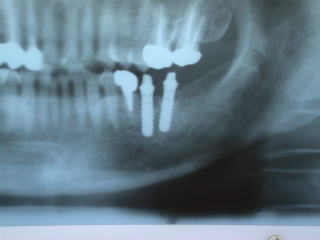

●インプラントのレントゲン写真例

下の奥歯の例です。

上の奥歯の例です。

上は上顎洞という骨空洞があり、インプラントの植立が困難な場合が多いです。

こちらのケースは左上の保険外延長ブリッジのロウ着部分が破損のためインプラントを入れて3歯連続冠にしました。